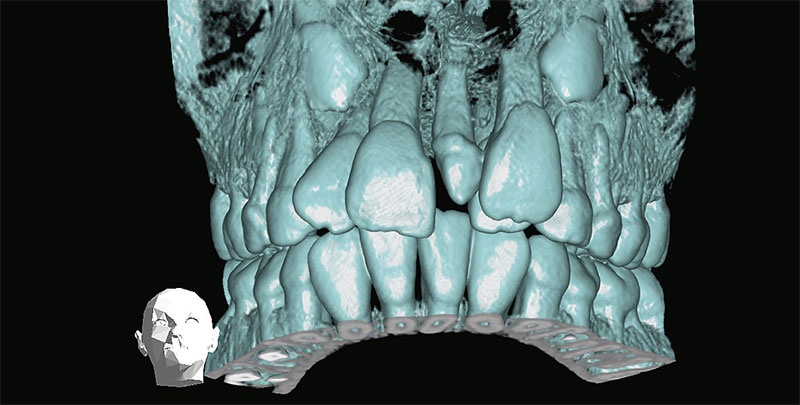

Ausgeprägtes Diastema zwischen 11/21 und Fehlstellung der lateralen Inzisiven aufgrund eines Mesiodens (3D-Bildrekonstruktion).